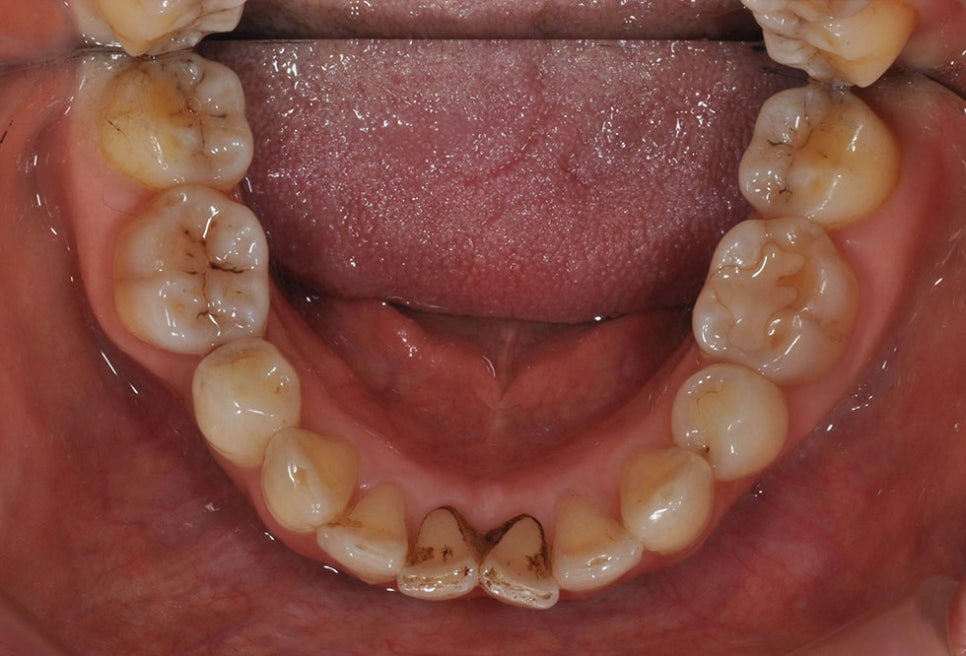

비뚤어진 치열의 경우에는

칫솔질을 해도 공간이 떠서

잘되지 않아 충치나 각종

잇몸 질병의 위험성이 높습니다.

치열이 바르지 않으면

부정교합으로 인해 음식을

먹을 때 저작 운동에 어려움이

생길 수 있습니다.

이처럼 비뚤어진 치아나

돌출입과 같은 부정교합은

심미적인 부분에도 큰 영향을

주지만 치아 건강에도 영향을

주기 때문에 부정교합이 있는

경우에는 교정 치료가 권장됩니다.